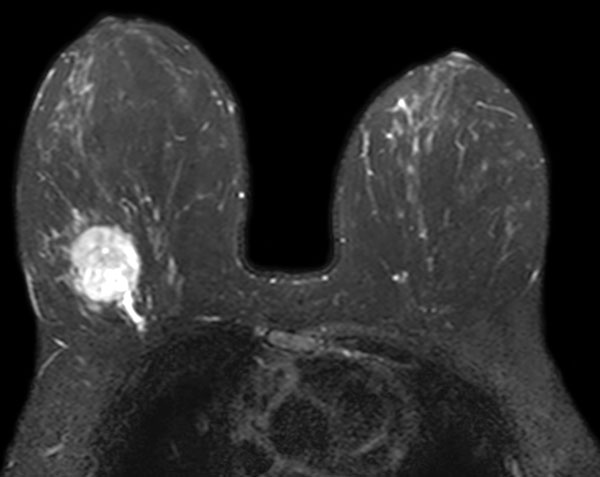

SmartBreast - dS Breast 7ch coil

Utrecht Medical Center, The Netherlands

Used Solution

• System

• Coil